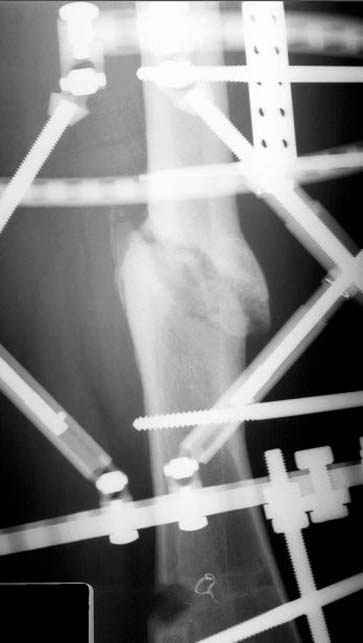

Несколько снимков из моей коллекции, чтобы разьяснить, почему мы до сих пор делаем различные варианты остеотомии.

N3 рисунок окончательный снимок, после операции моя рентгенограмма должен выглядеть примерно как эта картина. На N4 снимке клин перед удалением; N5 послеоперации 3 нед.; N6 окончательная рентгенограмма.

пластическая модель; и коррекция бедра аппаратом Илизарова.

Отправитель: Evgueny Tschekashkin 23 Ноябрь 2004, 21:28

Почему не замена гвоздя с рассверливанием, а аппарат?

Отправитель: Alexander Chelnokov 23 Ноябрь 2004, 21:29

Попробую угадать - была инфекция?

Узкий к-м канал - тонкий гвоздь- усталостный перелом дистальных винтов - развитие нестабильности и как ее результат остеолиз вокруг гвоздя - деформация анатомической оси бедра. Похоже, что я понял почему аппарат, а не новый гвоздь:-)